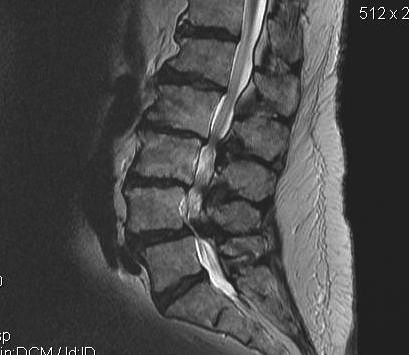

MRI

T2 Sagittal "MRI Myelogram"

Stenotic Measurement

A. Volume

- more accurate

- critical area is 100 mm2

B. AP diameter less accurate

- normal if > 12mm

- absolute stenosis if < 10mm

Intervertebral foramina

- no fat about nerve root

- reduced height